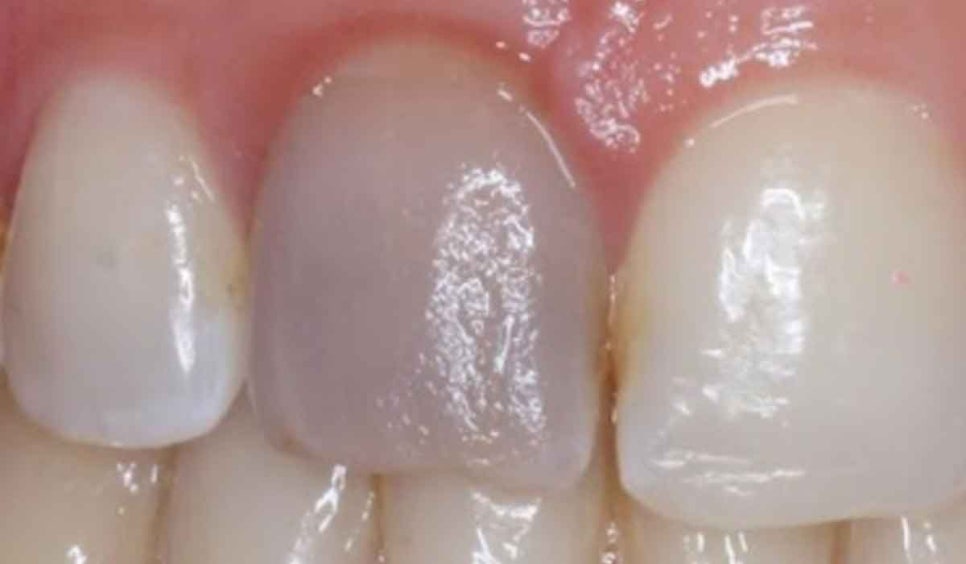

앞니는 작은 변화만 있어도 눈에 확 띄기 때문에

색이 탁해지거나 누렇게 변하면 많은 분들이 걱정하며 내원하시는데요.

겉으로 보기에는 깨끗한데

유독 한두 개 치아만 갑자기 어둡게 변하거나 누렇게 보이는 경우가 있습니다.

초진 구내 사진을 보면 눈에 잘 보이는 21번 앞니가 누렇게 색이 변해있는 것을 볼 수 있습니다.